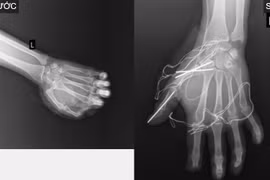

Nguy cơ mất toàn bộ bàn tay trái vì pháo nổ

Khi không may xảy ra tai nạn pháo nổ, người bị thương cần được băng bó tối thiểu, nẹp cố định và đến cơ sở y tế gần nhất, tránh mất thời gian vàng cấp cứu.